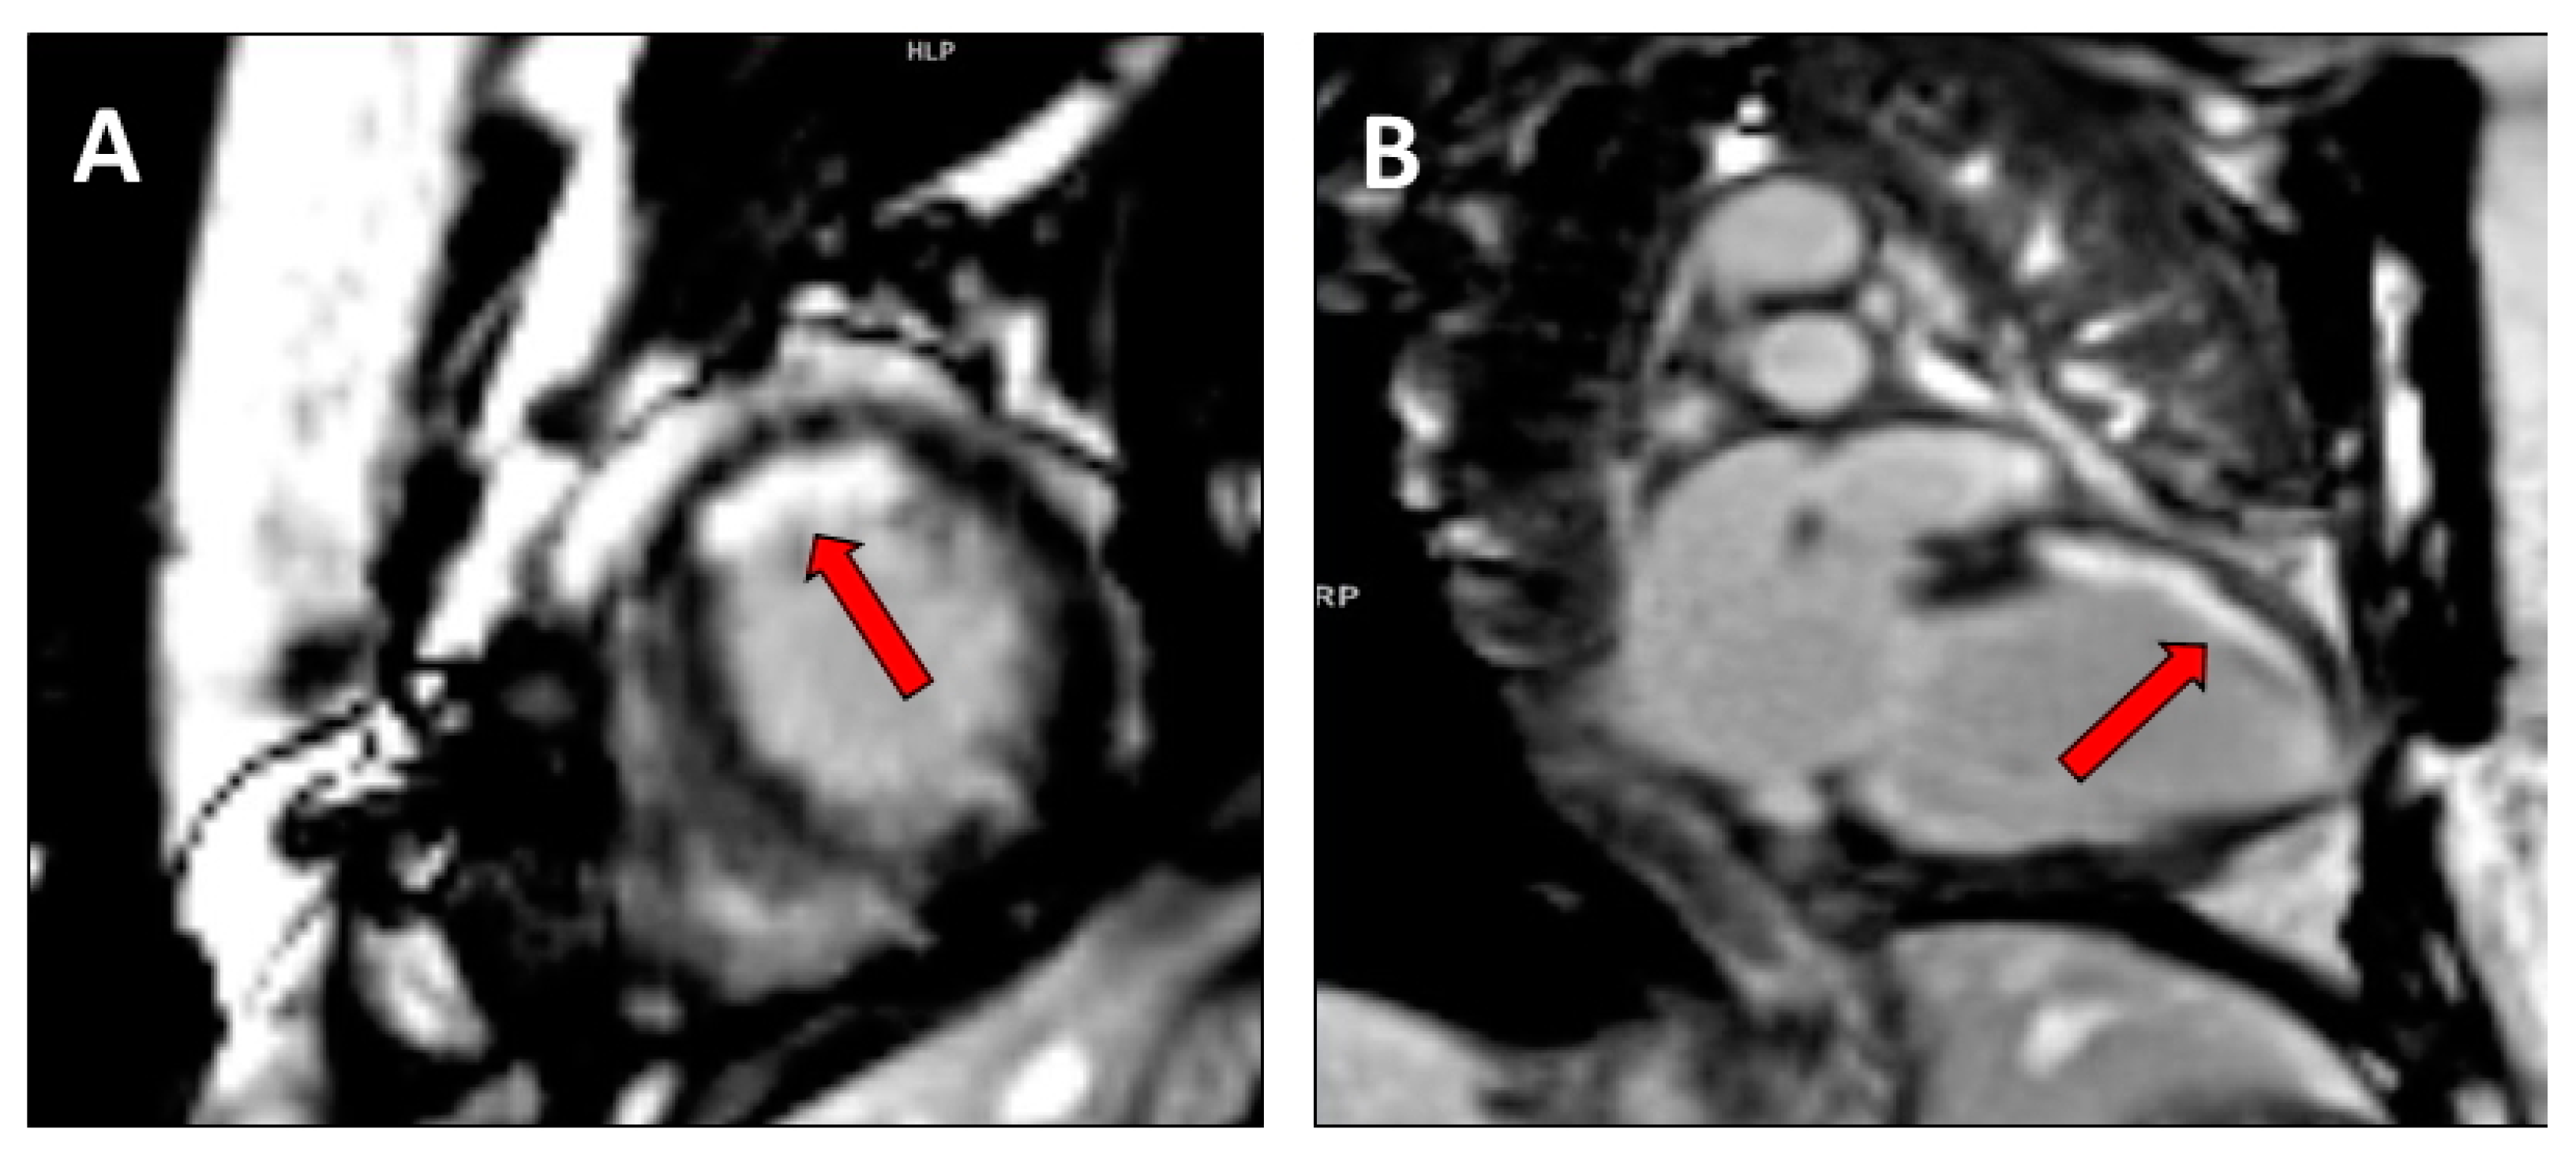

2.2. Assessment of Myocardial Contractile Reserve and Scar Burden

- Chalil, S.; Stegemann, B.; Muhyaldeen, S.; Khadjooi, K.; Smith, R.E.; Jordan, P.J.; Leyva, F. Intraventricular dyssynchrony predicts mortality and morbidity after cardiac resynchronization therapy: A study using cardiovascular magnetic resonance tissue synchronization imaging. J. Am. Coll. Cardiol. 2007, 50, 243–252. [Google Scholar] [CrossRef] [PubMed] [Green Version]

- Bilchick, K.C.; Dimaano, V.; Wu, K.C.; Helm, R.H.; Weiss, R.G.; Lima, J.A.; Berger, R.D.; Tomaselli, G.F.; Bluemke, D.A.; Halperin, H.R.; et al. Cardiac magnetic resonance assessment of dyssynchrony and myocardial scar predicts function class improvement following cardiac resynchronization therapy. JACC Cardiovasc. Imaging 2008, 1, 561–568. [Google Scholar] [CrossRef] [PubMed] [Green Version]

- Aalen, J.M.; Donal, E.; Larsen, C.K.; Duchenne, J.; Lederlin, M.; Cvijic, M.; Hubert, A.; Voros, G.; Leclercq, C.; Bogaert, J.; et al. Imaging predictors of response to cardiac resynchronization therapy: Left ventricular work asymmetry by echocardiography and septal viability by cardiac magnetic resonance. Eur. Heart J. 2020, in press. [Google Scholar] [CrossRef] [PubMed]

- Leyva, F.; Foley, P.W.; Chalil, S.; Ratib, K.; Smith, R.E.; Prinzen, F.; Auricchio, A. Cardiac resynchronization therapy guided by late gadolinium-enhancement cardiovascular magnetic resonance. J. Cardiovasc. Magn. Reson. 2011, 13, 29. [Google Scholar] [CrossRef] [Green Version]

- Taylor, R.J.; Umar, F.; Panting, J.R.; Stegemann, B.; Leyva, F. Left ventricular lead position, mechanical activation, and myocardial scar in relation to left ventricular reverse remodeling and clinical outcomes after cardiac resynchronization therapy: A feature-tracking and contrast-enhanced cardiovascular magnetic resonance study. Heart Rhythm. 2016, 13, 481–489. [Google Scholar] [PubMed]